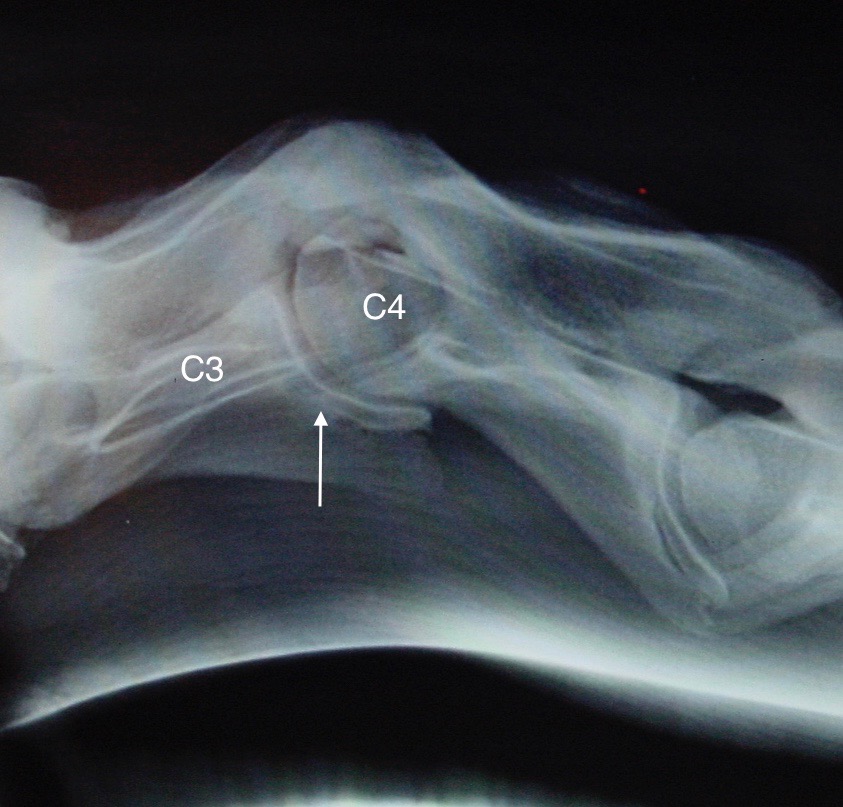

Další krok v diagnostice problémů krku je zhotovení rentgenových snímků celé krční páteře (od lebky po první hrudní obratel). Toto vyšetření může odhalit četné abnormality, například zúžení páteřního kanálu, subluxaci obratlů (obr. 3), závažnou artrózu nebo zlomeniny.

Obrázek 3: Závažná subluxace C3–C4